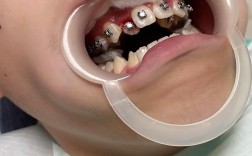

矫正牙齿的本质是牙齿在牙槽骨中的移动,这个过程必然伴随疼痛,25岁的骨骼已发育完全,牙槽骨密度更高,牙齿移动的阻力比青少年更大,因此疼痛感可能更强烈且持久,初期戴牙套后的1-2周,牙齿对咬合、刷牙、甚至说话都会产生敏感酸痛,有人只能喝粥、吃流食,体重下降5公斤;每次调整弓丝后,疼痛会再次加剧,持续3-5天才能缓解,更让人难以忍受的是,牙套边缘可能摩擦口腔黏膜,导致反复发作的溃疡,即使使用正畸蜡也只能暂时缓解,有矫正者回忆,曾因溃疡严重到无法正常进食,只能靠打营养液维持,最终不得不暂停矫正一周,牙齿移动过程中可能出现暂时性松动,让矫正者时刻担心“牙齿会不会掉”,这种对口腔健康的焦虑,进一步放大了痛苦体验。

25岁是社交活跃的年纪,对外在形象的关注度极高,而牙套带来的“钢牙”形象,却成了社交中的“隐形障碍”,尽管有陶瓷牙套、隐形牙套等选择,但金属托槽在阳光下仍会反光,隐形牙套戴在嘴上虽不明显,却会在说话或大笑时显露“塑料痕迹”,有女生分享,矫正后曾因同事调侃“你牙套上沾着韭菜”而尴尬一整天,此后再也不敢在食堂吃饭,只能每天带饭;还有人因担心牙套影响约会形象,多次推脱邀约,甚至产生自卑心理,更麻烦的是,矫正期间牙齿会经历“丑丑的阶段”:门牙可能因移动前突而显得更凸,牙缝在关闭时可能变大,这些变化在矫正初期尤为明显,让许多追求“立竿见影”效果的年轻人难以接受,开始怀疑“矫正真的能变美吗?”